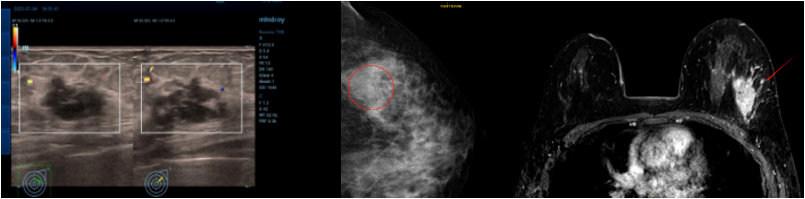

乳腺彩超:左侧乳腺实性结节(1-2点),28×18mm,BIRADS 4B类。左侧腋窝淋巴结肿大,15×11mm。

乳腺钼靶:左乳外上象限钙化灶及结节影,BI-RADS 4B类。

乳腺MRI:左乳外上象限肿块,大小约29mm×19mm,考虑乳腺癌,BI-RADS 6类。

乳腺彩超:左侧乳腺皮肤水肿增厚,约4.7mm。左乳部分切除术后,皮层明显增厚,左乳内结构显示不满意,BIRADS 0。右侧乳腺未见明显占位病变,BIRADS 1类。左侧腋窝区未见异常淋巴结。右侧腋窝淋巴结肿大,最大约33×15mm,皮质明显增厚,部分门型结构消失,性质待查。

乳腺MR:左乳上象限乳腺癌治疗后改变,病灶范围较前增大,较大范围约30mm×31mm×29mm;左侧乳腺多发结节、乳晕、皮肤增厚及右腋窝增大淋巴结,大者直径24mm,考虑转移。右乳多发囊性病灶,右乳背景多发轻度强化,考虑良性改变,BI-RADS 3类。